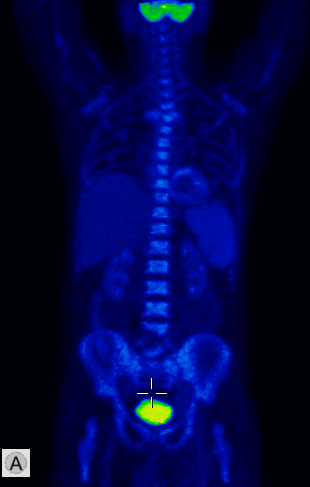

The most important and most commonly used isotope examination of the musculoskeletal system is bone scintigraphy. During the examination the natural component of bone- pyrophosphate analogues, technetium labeled diphosphonate radiopharmaceuticals are used. Following intravenous injection, the radiotracer binds to the hydroxyapatite crystals of the bone. Its uptake in the bones is influenced by blood supply and osteoblast activity. The unnecessary, unbound radiotracers are excreted through the kidneys after about 2-3 hours, scintigraphy is performed during this late metabolic phase. This method consistently depicts bone structure and areas where increased or decreased metabolic activity persist. Usually, whole-body planar images are obtained from an anterior and a posterior direction and additional, optional lateral and oblique measurements can also be performed of targeted lesions if necessary. (Figure 3.)

3. Whole body bone scintigraphy, anterior (a) and posterior (b) acquisitions. Normal findings.